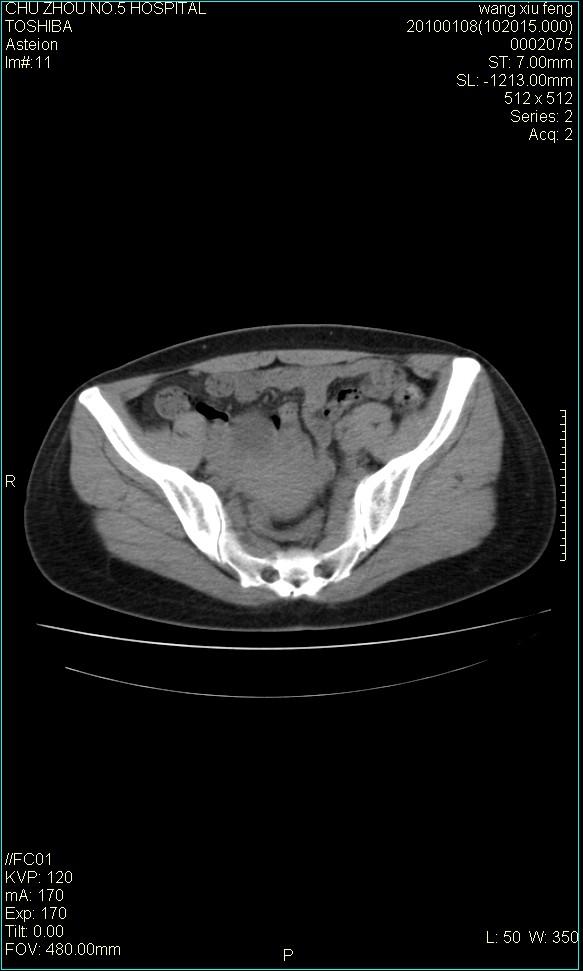

f-41,左乳腺ca术后4年,b超示:子宫右上方囊性包块约5.5*3.4cm,前日行胸部ct平扫未见明显异常。

考虑右侧卵巢囊腺瘤?

右侧卵巢囊肿或小囊腺瘤。

考虑右侧卵巢囊腺瘤。

考虑右侧卵巢囊性占位性病变(囊肿?囊腺瘤?)。